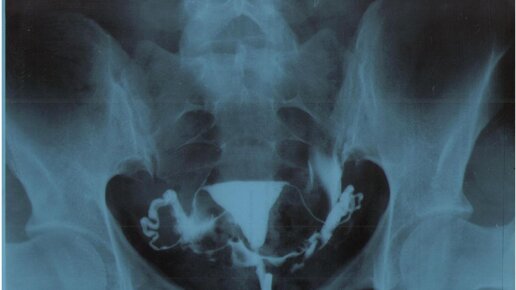

Одним из наиболее вероятных обстоятельств, способствующих бесплодию, является непроходимость маточных (фаллопиевых) труб. Узнать, есть ли непроходимость можно при помощи гистеросальпингографии (ГСГ). Почему возникает бесплодие? Бесплодием считается состояние женщины репродуктивного возраста, при котором беременность не возникает в пределах года постоянных попыток зачатия, то есть с периодичностью не менее двух раз в неделю, при отсутствии предохранения. Этот диагноз ставит врач-гинеколог, а перед...

Всех приветствую на моем канале! Меня зовут Яна. Моему сыну 2 года и врачи подозревают у него аутизм. Как я писала в предыдущей статье, беременность у меня была поздней и первой. Самостоятельно забеременеть у меня не получалось. На тот момент мне было 40 лет. Все какие нужно обследования и анализы я сдала, всё было в порядке. Врач-гинеколог, у которой я наблюдалась, предложила мне проверить проходимость маточных труб. С возрастом в маточных трубах образуются спайки, которые вызывают непроходимость, и соответственно беременность не наступает...